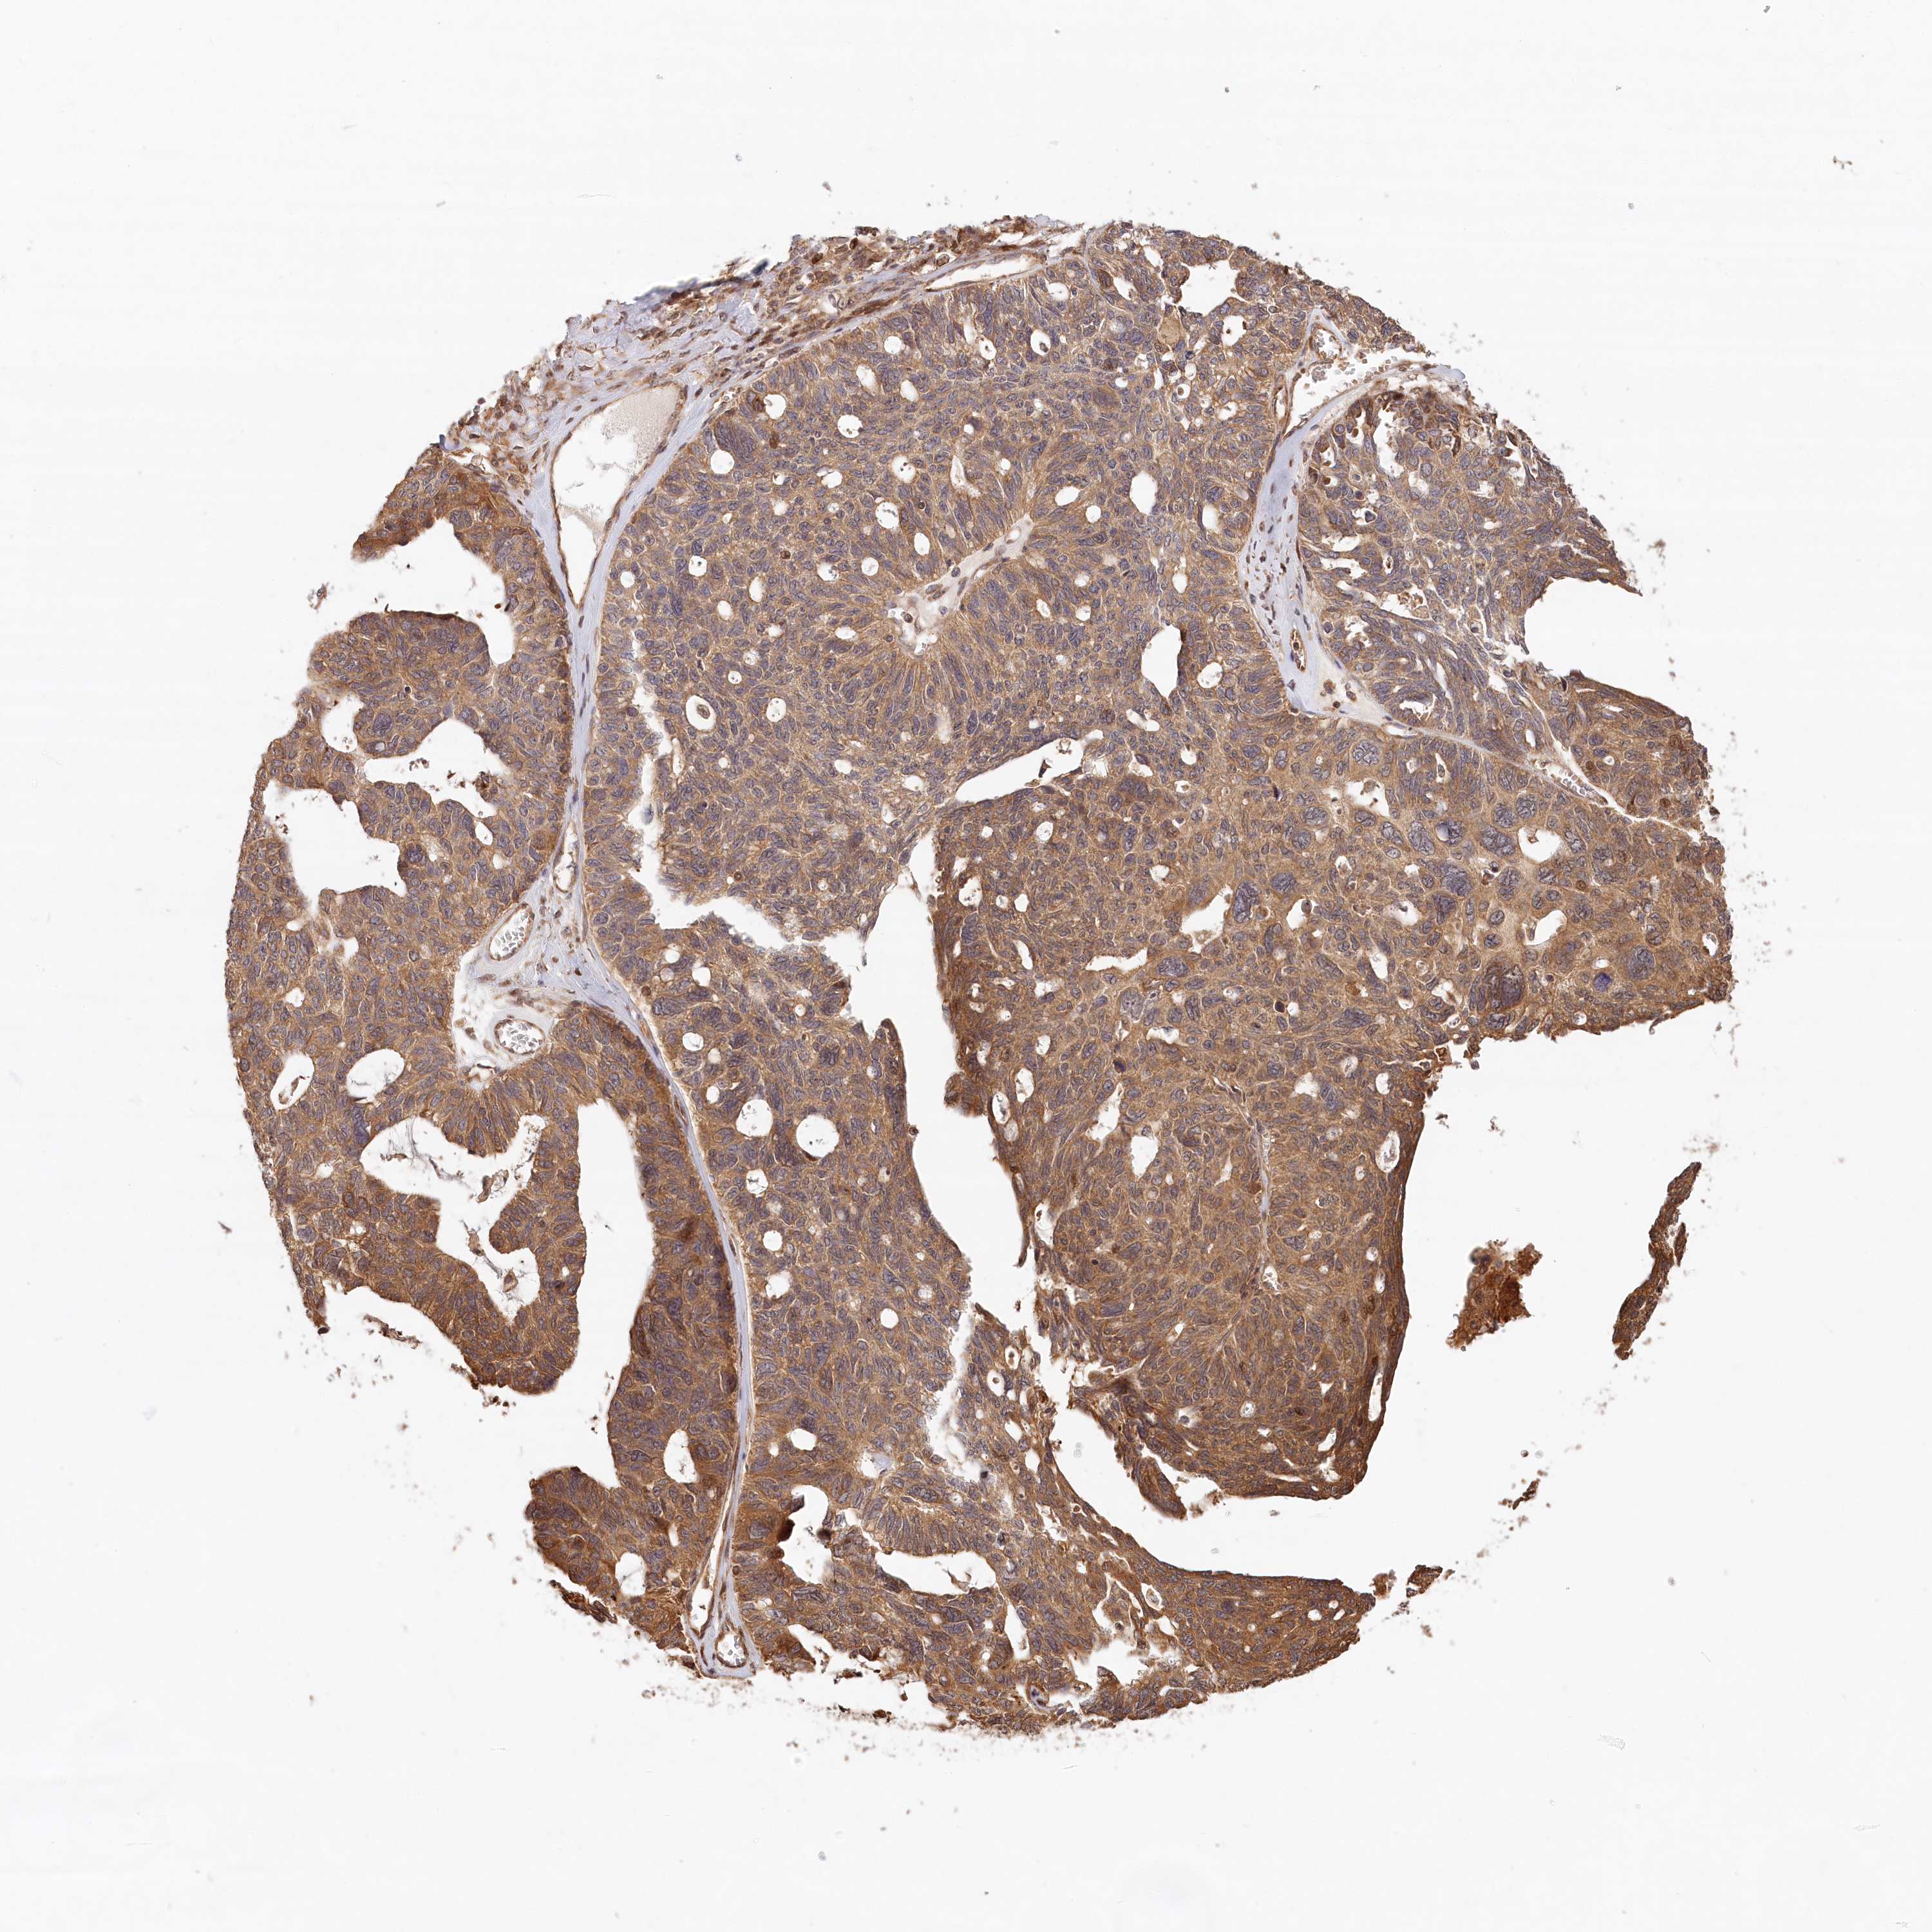

OVARIAN CANCER - Protein expressioni

A mouse-over function shows sample information and annotation data. Click on an image to view it in a full screen mode. Samples can be filtered based on level of antibody staining by selecting one or several of the following categories: high, medium, low and not detected. The assay and annotation is described here.

Note that samples used for immunohistochemistry by the Human Protein Atlas do not correspond to samples in the TCGA dataset.

Antibody stainingi

Antibody staining in the annotated cell types in the current human tissue is reported as not detected, low, medium, or high, based on conventional immunohistochemistry profiling in selected tissues. This score is based on the combination of the staining intensity and fraction of stained cells.

Each image is clickable and will lead to virtual microscopy that enables deeper exploration of all samples and also displays staining intensity scores, fraction scores and subcellular localization as well as patient and tissue information for each sample.

Antibody HPA032060

Antibody HPA032062

Antibody CAB034116

Staining

High

Medium

Low

Not detected

Intensity

Strong

Moderate

Weak

Negative

Quantity

>75%

75%-25%

<25%

None

Location

Nuclear

Cytoplasmic/membranous

Cytoplasmic/membranous,nuclear

Cystadenocarcinoma, serous, NOS

Carcinoma, endometroid

Cystadenocarcinoma, mucinous, NOS

Carcinoma, NOS